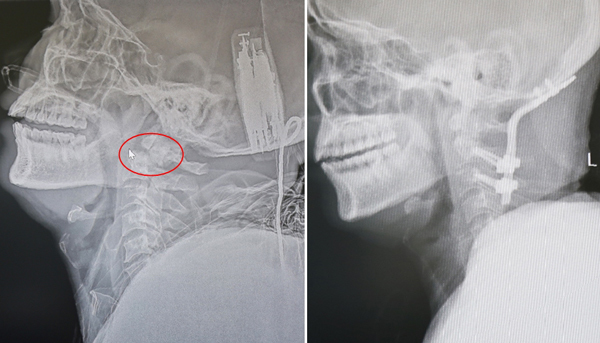

Kết quả kiểm tra và chụp cắt lớp vi tính cho thấy, anh H. bị đa chấn thương, chấn thương đốt sống cổ (vỡ mỏm nha C2, trượt C1-C2 - trụ nâng đỡ đầu), chèn ép tủy cổ, chấn thương ngực kín, gãy đốt sống ngực, tràn dịch màng phổi.

| Hình ảnh tổn thương tại thời điểm bệnh nhân nhập viện (ảnh trái) và hình ảnh sau khi cố định |

Bệnh nhân được cố định cột sống cổ C2 – C3 với xương sọ vùng chẩm, cắt bỏ khung sau C1 để giải phóng chèn ép tuỷ. Cuộc mổ thành công sau 3 tiếng căng thẳng.